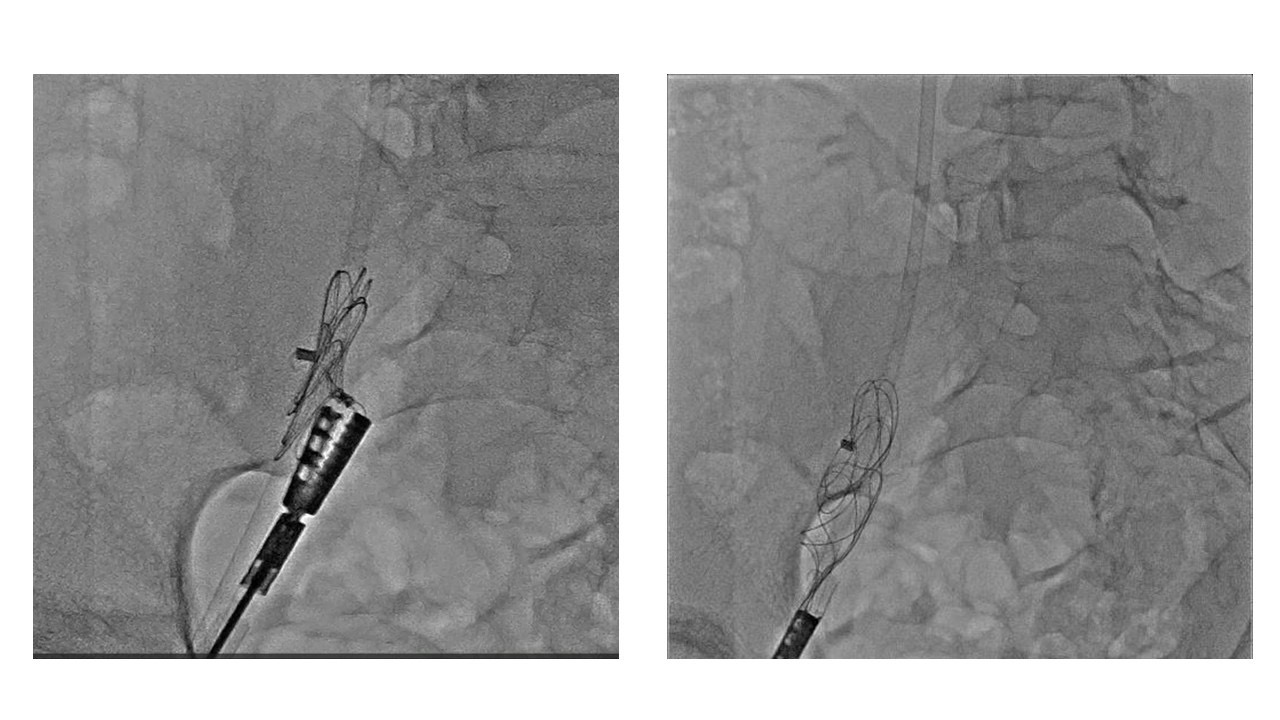

The GCA was deployed as usual with fluoro and ICE images. However, the device gradually began to move inappropriately, and we understood it hadn¡¯t been deployed properly. Thus, we decided to retrieve and change the device. At first, we tried to retrieve it still attaching the atrial septum using standard EN snare, and caught the lock loop to remove from the atrial septum, however it came off the snare catheter because of weak locking loop wire. Next, we caught the floating device in right atrium with biopsy forceps and succeeded to pull it down to the iliac vein. Unfortunately, we could not move the occluder into the sheath, as its slippery designed hub and bulky device body even using combination of snare with biopsy forceps. Finally, we decided to insert 16 Fr. size sheath to use Crocodile Forceps for surgical gallbladder operation like laparoscopic cholecystectomy as its powerful gripping force.

We experienced a very difficult procedure in which ordinary snare and forceps were useless to retrieve the migrating occluder. In the end, we were able to retrieve the GCA occluder using strong crocodile forceps usually used in laparoscopic cholecystectomy, and closed the ASD with Figulla Flex 2 occluder.